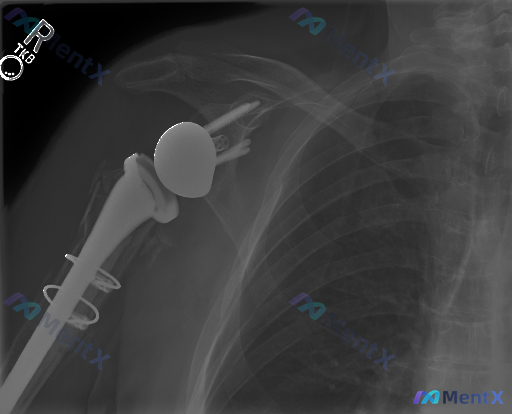

整理到一张很有意思的术后影像读片材料——一张右侧肩关节正位X光片。 第一眼看到“异常”很明显,但最关键的是:哪些是术后预期的改变?哪些是真正需要警惕的病理异常? 先不把所有分析放出来,大家先看这张片子的核心描述: - 可见“反置”的关节结构:关节盂侧是金属球体,肱骨侧是凹面杯 - 肱骨近端有假体柄,...